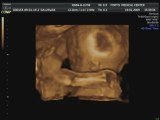

Bb23s_1.VolCine